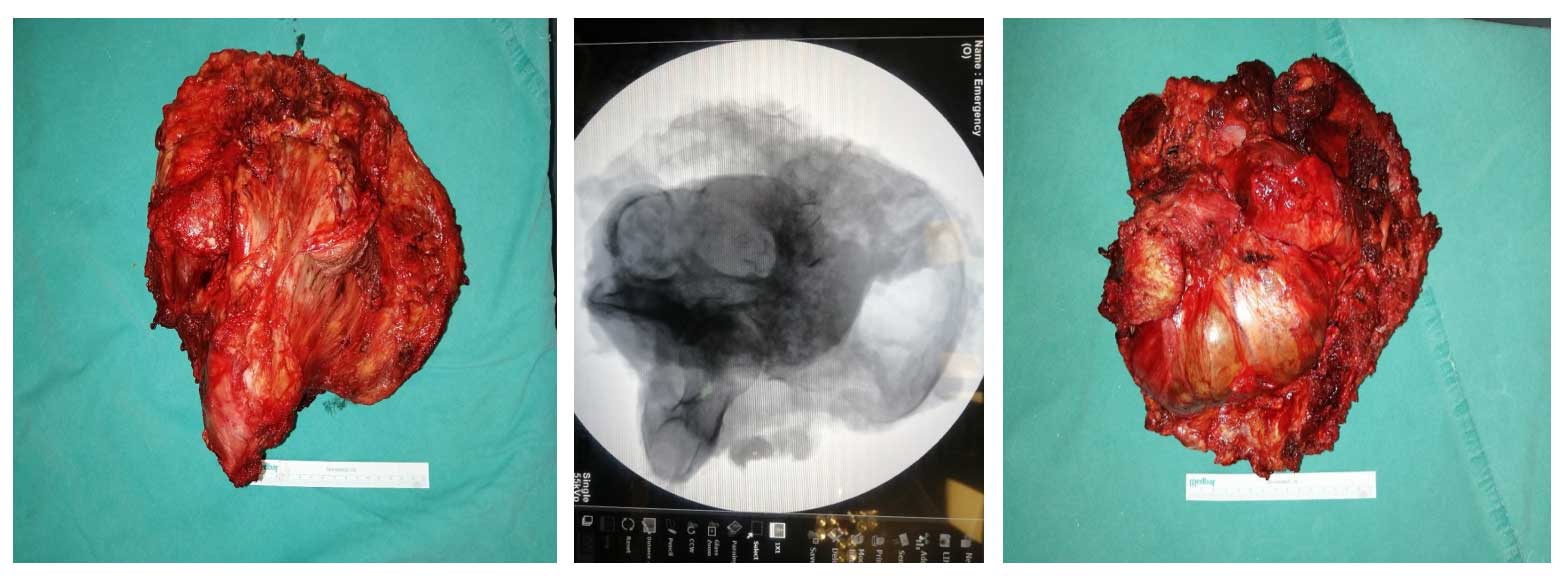

Ameliyat Esnası: Çıkarılan tümör dokusunun klinik ve skopi görüntüsü.